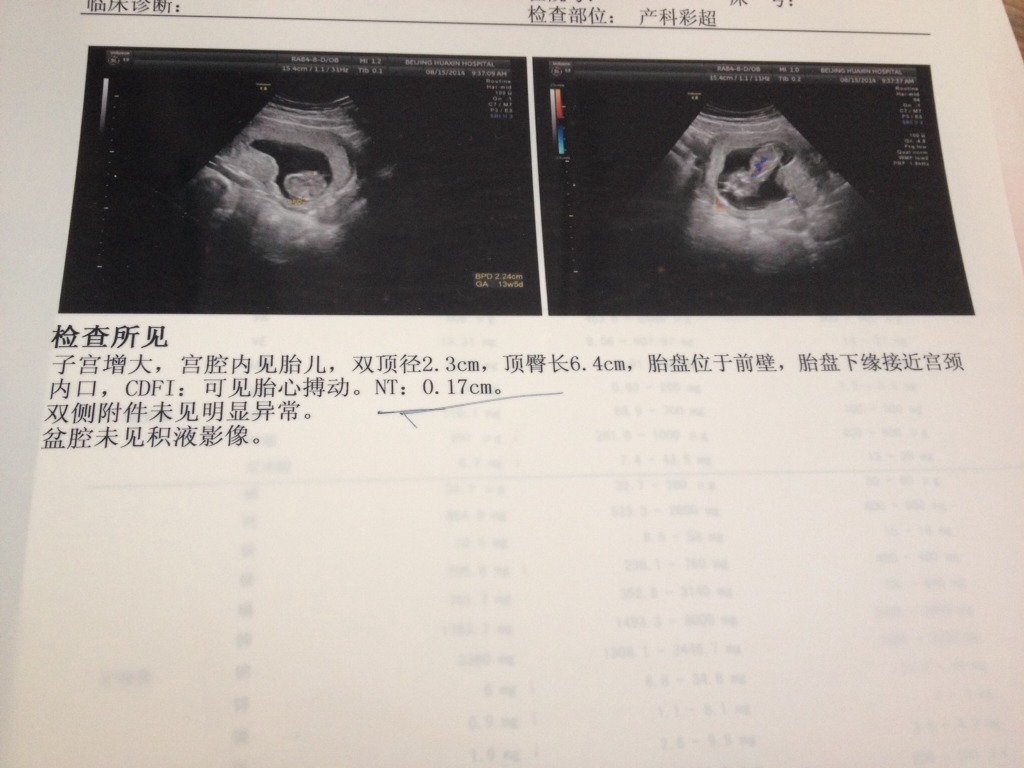

12w+6,突然出血,医生说长不上去就上前置胎盘,容易大出血好可怕啊 怎么才能长上去呢 b超能看 12w+6,突然出血,医生说长不上去就上前置胎盘,容易大出血。好可怕啊。怎么才能长上去呢。b超能看出小孩四肢么?哪为了解前置胎盘和会看bc,求指点。 点击展开 pamela_TT 2014-08-16 11:34 为您推荐: 其他回答 你好,你这样的状况最好就是尽量的注意卧床休息了,平时的时候也是不能吃生冷寒凉的食物 黄宇医生 2014-08-16 16:00 相关问题 前置胎盘前两天出血,要是自己家开车躺上去,会不会发生大出血 我是中央前置胎盘,好郁闷喔!手术期间会大出血,必须输血,这个孩子代价好大喔! 我是中央前置胎盘,好郁闷喔!手术期间会大出血,必须输血,这个孩子代价好大喔!